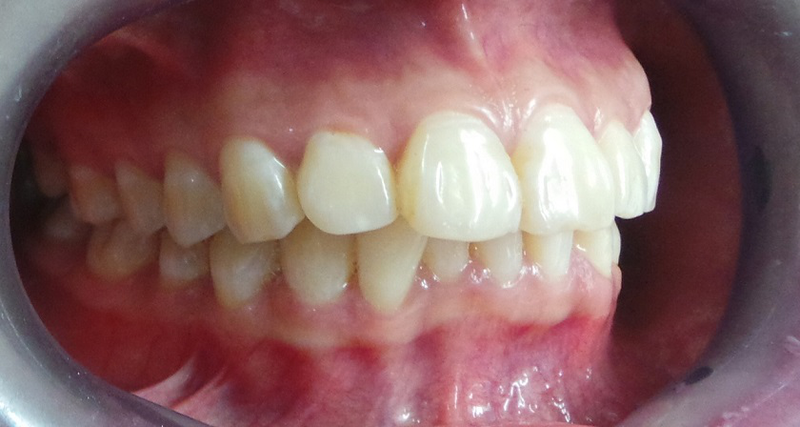

Với răng hô ở mức độ nhẹ đến trung bình, phương pháp bọc răng sứ có thể được áp dụng. Thông qua đó cải thiện hình thể răng và điều chỉnh phần nào khớp cắn. Tuy nhiên, khi bị hô nặng, việc bọc sứ đòi hỏi phải mài mô răng thật với tỷ lệ lớn. Từ đó gây xâm lấn sâu và làm suy yếu cấu trúc răng. Do đó, bác sĩ cần đánh giá kỹ lưỡng để lựa chọn phương pháp điều trị phù hợp. Nó có thể bao gồm niềng răng hoặc phẫu thuật chỉnh hình trong các trường hợp phức tạp.

Vừa rồi chúng ta đã biết được bọc răng sứ có hết hô không. Lúc này điều nhiều người quan tâm đó là những lợi ích của bọc răng sứ đối với răng hô. Đây là một trong những giải pháp chỉnh hình răng hiện đại. Cùng với đó là được nhiều khách hàng lựa chọn nhờ độ hiệu quả và thẩm mỹ cao. Phương pháp này không chỉ giúp cải thiện tình trạng răng hô. Nó còn khắc phục đồng thời nhiều vấn đề khác liên quan đến hình dáng và màu sắc răng.

- An toàn, phù hợp với các trường hợp răng hô nhẹ đến trung bình do sai lệch vị trí răng.